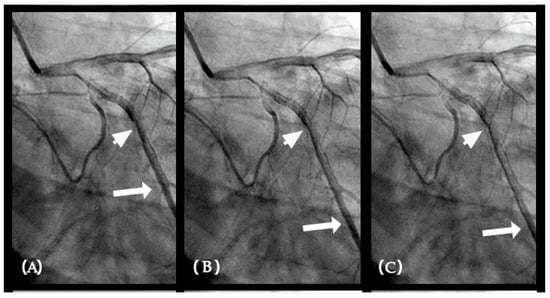

IN VIVO Coronary Flow Analysis. Angiographic Compression and Rarefaction Zones. Building on an advanced understanding of pressure wave reflections in pipes from an acoustic perspective, this investigation applied acoustic principles to analyze flow dynamics in coronary arteries. The primary objective was to delineate and quantify regions within the coronary arteries characterized by pockets of high-contrast density (compression) and moderate-contrast density (rarefaction), identified as antinodes (Figure 15A,B). Conversely, areas with minimal contrast were designated as nodes. These classifications were finalized at the end of the second cardiac cycle when the contrast was almost all washed out, leaving pockets of contrast which most likely were zones of compression or rarefaction (labeled as antinodes). The needs for identifying the five zones of compression and rarefaction (antinodes) and the minimal or lesion-free segments (nodes) within a coronary artery are listed in Table 4.

The secondary objective was to examine the relationship between antinodes and the presence of coronary stenoses, as well as between nodes and minimally diseased or lesion-free coronary segments. Ultimately, the investigation aimed to establish antinodes as potential markers for high-pressure surges linked to intimal damage. These locations of antinodes are used to construct a coronary acoustic activity (or action) map, enabling the identification of existing lesions, forecasting the progression of current lesions, and predicting the development of potential future lesions. Table 5 outlines the protocol on how to identify and label the five zones of compression and rarefaction (antinodes) and the minimal or lesion-free segments (nodes) within the coronary arteries. The protocol to identify the antinodes of compression and rarefaction and the nodes in between the antinodes uses the novel coronary dynamic angiographic technique. The protocol is listed in Table 5 and Figure 16A–E.

FIRST Compression Zone with High Contrast Concentration. Angiographic Identification. During diastole, coronary blood flow reaches a relatively high velocity. At the onset of systole, the contraction of the left ventricle abruptly interrupts this flow, triggering a water hammer effect. This results in the formation of a retrograde pressure wave, which collides with the antegrade flow at a critical timing when diastole transitions into systole. The initial reflection point, designated as location 1, is characterized by pockets of prolonged concentration of contrast agent, seen as a disorganized mixing of dark (contrast) and light (blood) materials (blue arrow in Figure 16E). These black-and-white pockets may signify turbulent flow, mirroring the surge of pressure in the local area (Figure 16A–D).

Mechanism of Damage. At location 1, damage mechanisms are likely driven by localized pressure spikes, stress concentrations, or repeated high-pressure cycles (vibrations), which induce deformation, cracking, or microtears in the intimal layer. These disruptions facilitate the migration of low-density lipoprotein (LDL) cholesterol into the subintimal space, initiating the atherosclerotic cascade (blue arrow in Figure 16E).

Clinical Relevance. The lesion at this location is very important because this is the most common lesion in the right coronary artery (RCA) and the most common location for ST elevation myocardial infarction in the RCA [35]. The reason is because this is the location where the pressure wave from water hammer hits first in its retrograde reflection, when diastole transitions to systole.

CRITICAL THINKING. High Concentration of Contrast at location 1 as a Marker of Compression Activity. During a typical cardiac cycle, antegrade blood flow accelerates during diastole and transitions rapidly into the systole, initiating a water hammer phenomenon that generates a retrograde pressure wave. This retrograde wave propagates at nearly the speed of sound and undergoes multiple reflections within one or two diastole–systole cycles along the length of a coronary artery. These reflections produce hundreds of retrograde pressure waves, which may synchronize with antegrade waves to form resonant patterns or, conversely, cancel out. The wave reflections occur at distinct locations: the diastole-to-systole junction (location 1), the coronary artery ostium (location 4), and the systole-to-diastole junction (location 2). The resulting wave dynamics display features of acoustic resonance, with regions of high contrast concentration corresponding to antinodes—pressure peaks associated with arterial damage or the progression of atherosclerosis (Figure 16E). High-contrast regions at locations 1 and 4, observed in coronary angiography, likely represent zones of compression and rarefaction, indicative of pressure surges that may compromise the intimal layer. The critical challenge lies in determining how these observations and hypotheses can be rigorously validated.